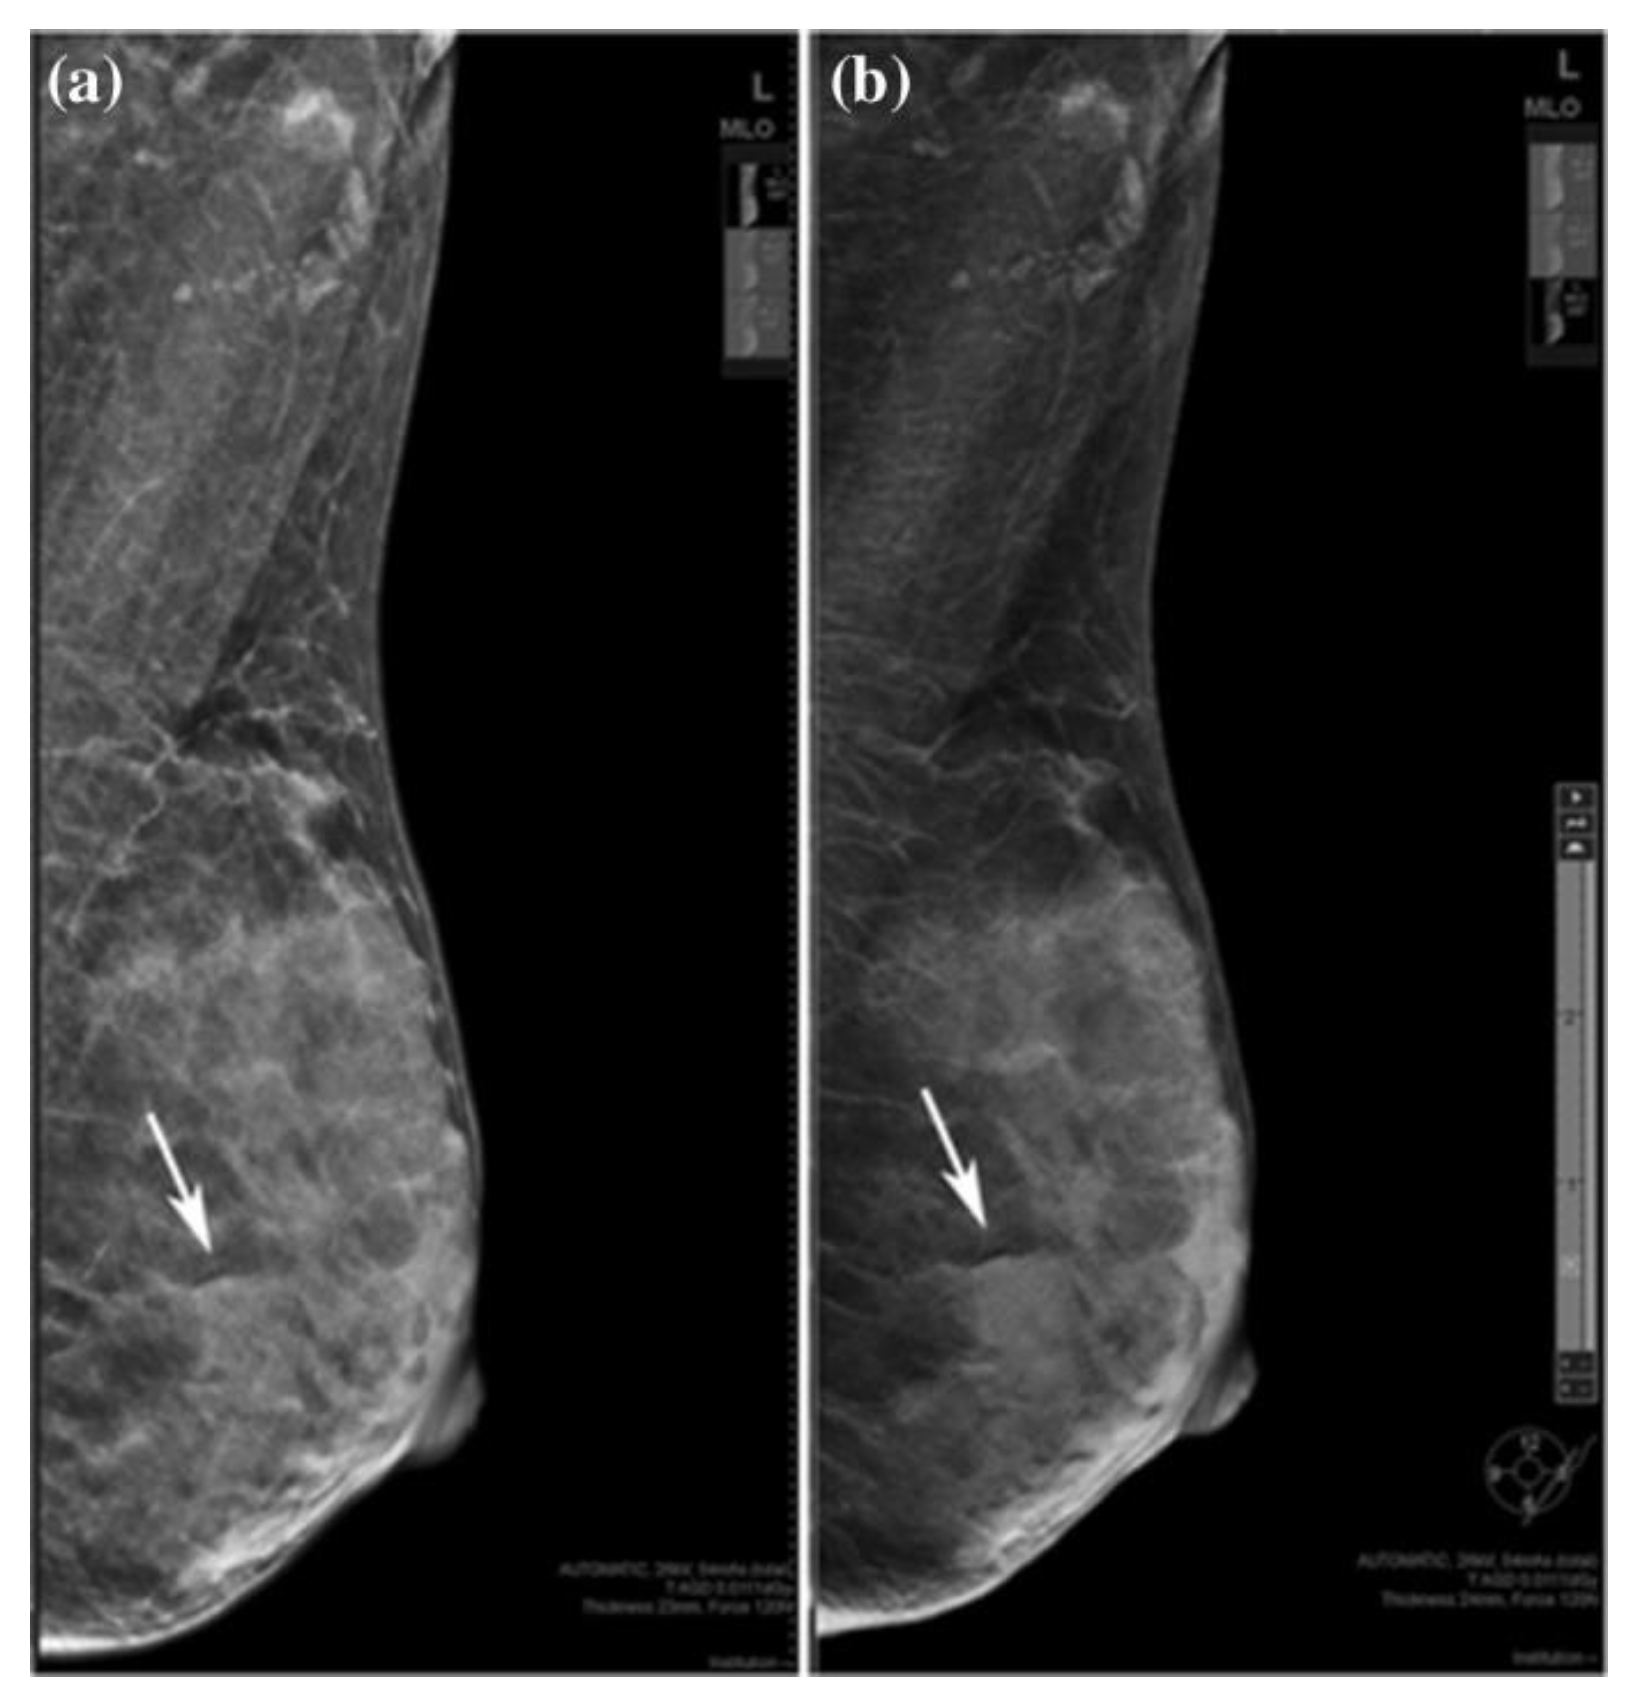

2.2. Digital Breast Tomosynthesis (DBT)

- Østerås, B.H.; Martinsen, A.C.T.; Gullien, R.; Skaane, P. Digital Mammography versus Breast Tomosynthesis: Impact of Breast Density on Diagnostic Performance in Population-based Screening. Radiology 2019, 293, 60–68. [Google Scholar] [CrossRef]

- Lee, S.H.; Jang, M.J.; Kim, S.M.; Yun, B.L.; Rim, J.; Chang, J.M.; Kim, B.; Choi, H.Y. Factors affecting breast cancer detectability on digital breast tomosynthesis and two-dimensional digital mammography in patients with dense breasts. Korean J. Radiol. 2019, 20, 58–68. [Google Scholar] [CrossRef]

- Yi, A.; Chang, J.M.; Shin, S.U.; Chu, A.J.; Cho, N.; Noh, D.-Y.; Moon, W.K. Detection of noncalcified breast cancer in patients with extremely dense breasts using digital breast tomosynthesis compared with full-field digital mammography. Br. J. Radiol. 2019, 92, 20180101. [Google Scholar] [CrossRef]